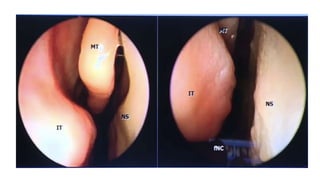

This document discusses the microanatomy of the sellar and suprasellar regions as well as operative approaches for accessing these areas. It describes the bones, venous connections, arterial relationships and incisura spaces in the regions. Several surgical approaches are mentioned, including sublabial, transseptal, endonasal, and subfrontal transfrontal transsphenoidal approaches. Key anatomical structures like the optic chiasm, carotid protuberance, cavernous sinus and clival indentation are located using an "owl eye" panoramic view of the fetal face mimicking centers.